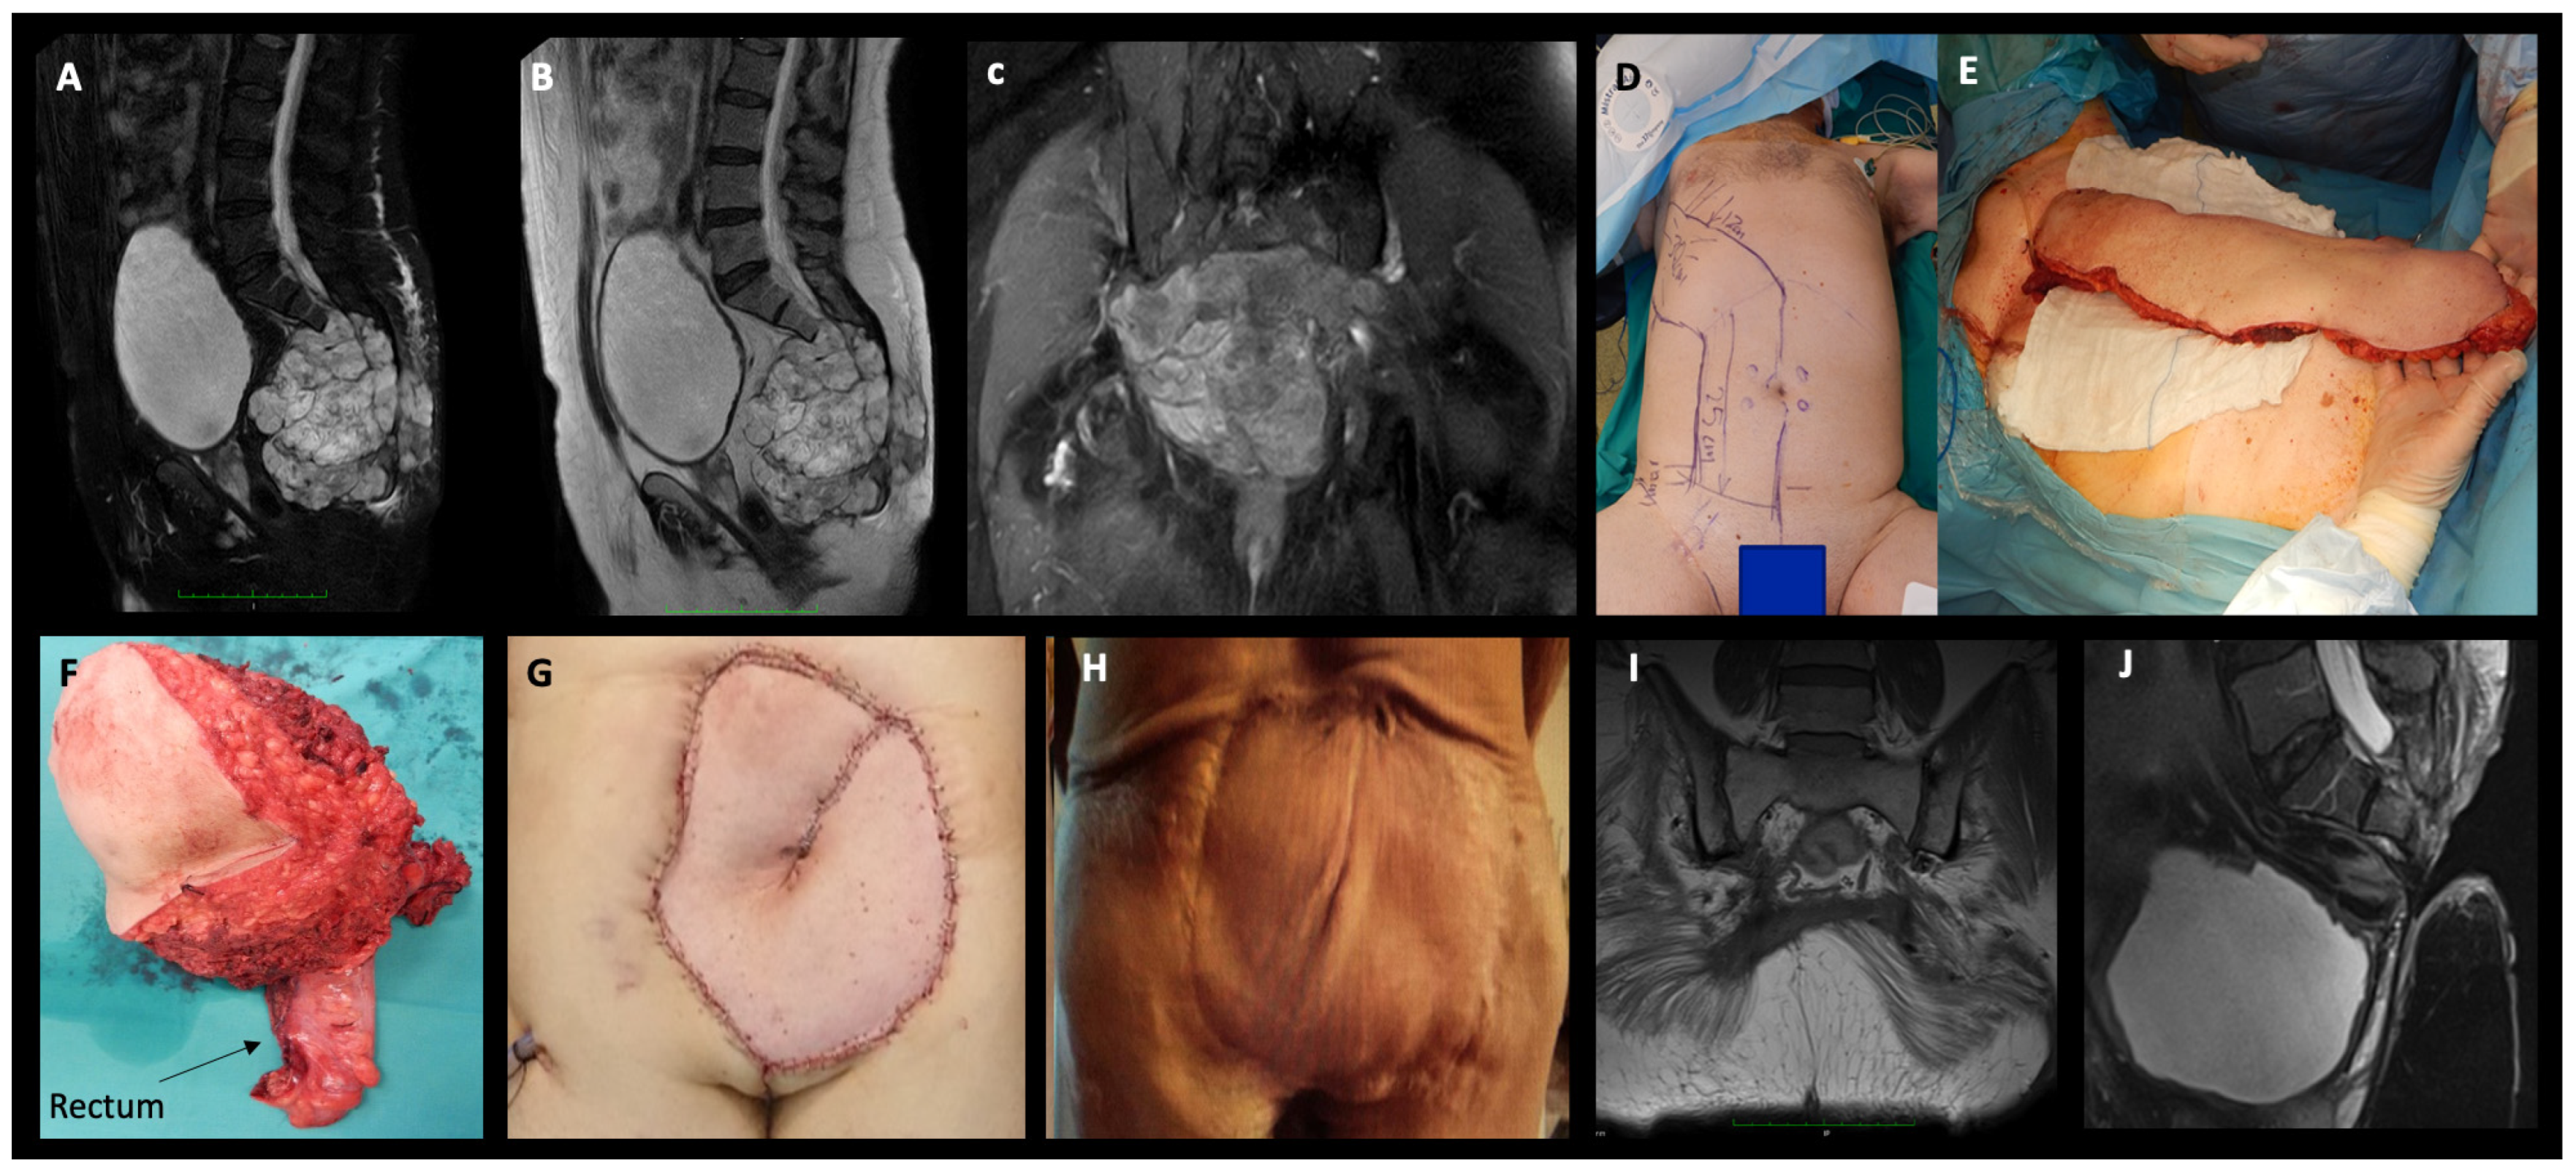

In total, 8 patients (29.6%) required a colostomy, and 10/27 patients (37%) required flap coverage due to extensive posterior soft tissue deficit, 5/10 of which were bilateral gluteal advancements, and another 5/10 were pedicled transpelvic vertical rectus abdominis myocutaneous flaps supplied by the inferior epigastric vessels (VRAM) (Figure 2).

Figure 2.

(A,B) T2-weighted with fat suppression and T2-weighted MRI sagittal views showing an S2 level sacral chordoma (male, 62 year), (C) postcontrast T1-weighted with fat suppression coronal MRI view showing dorsal soft tissue and gluteus maximus infiltration by the tumor (D,E) intraoperative photographs showing preparation and harvest of the VRAM flap, (F) photograph of the resected specimen showing en-bloc resection of the tumor with the skin and part of the rectum attached (combined approach), (G) restoration of the soft tissue defect with the VRAM flap, (H) satisfactory wound healing result without complications 1 year postoperatively, (I,J) T1-weighted coronal MRI view and T2-weighted with fat suppression sagittal MRI view, respectively, showing no local recurrence at 1 year postoperative follow-up.